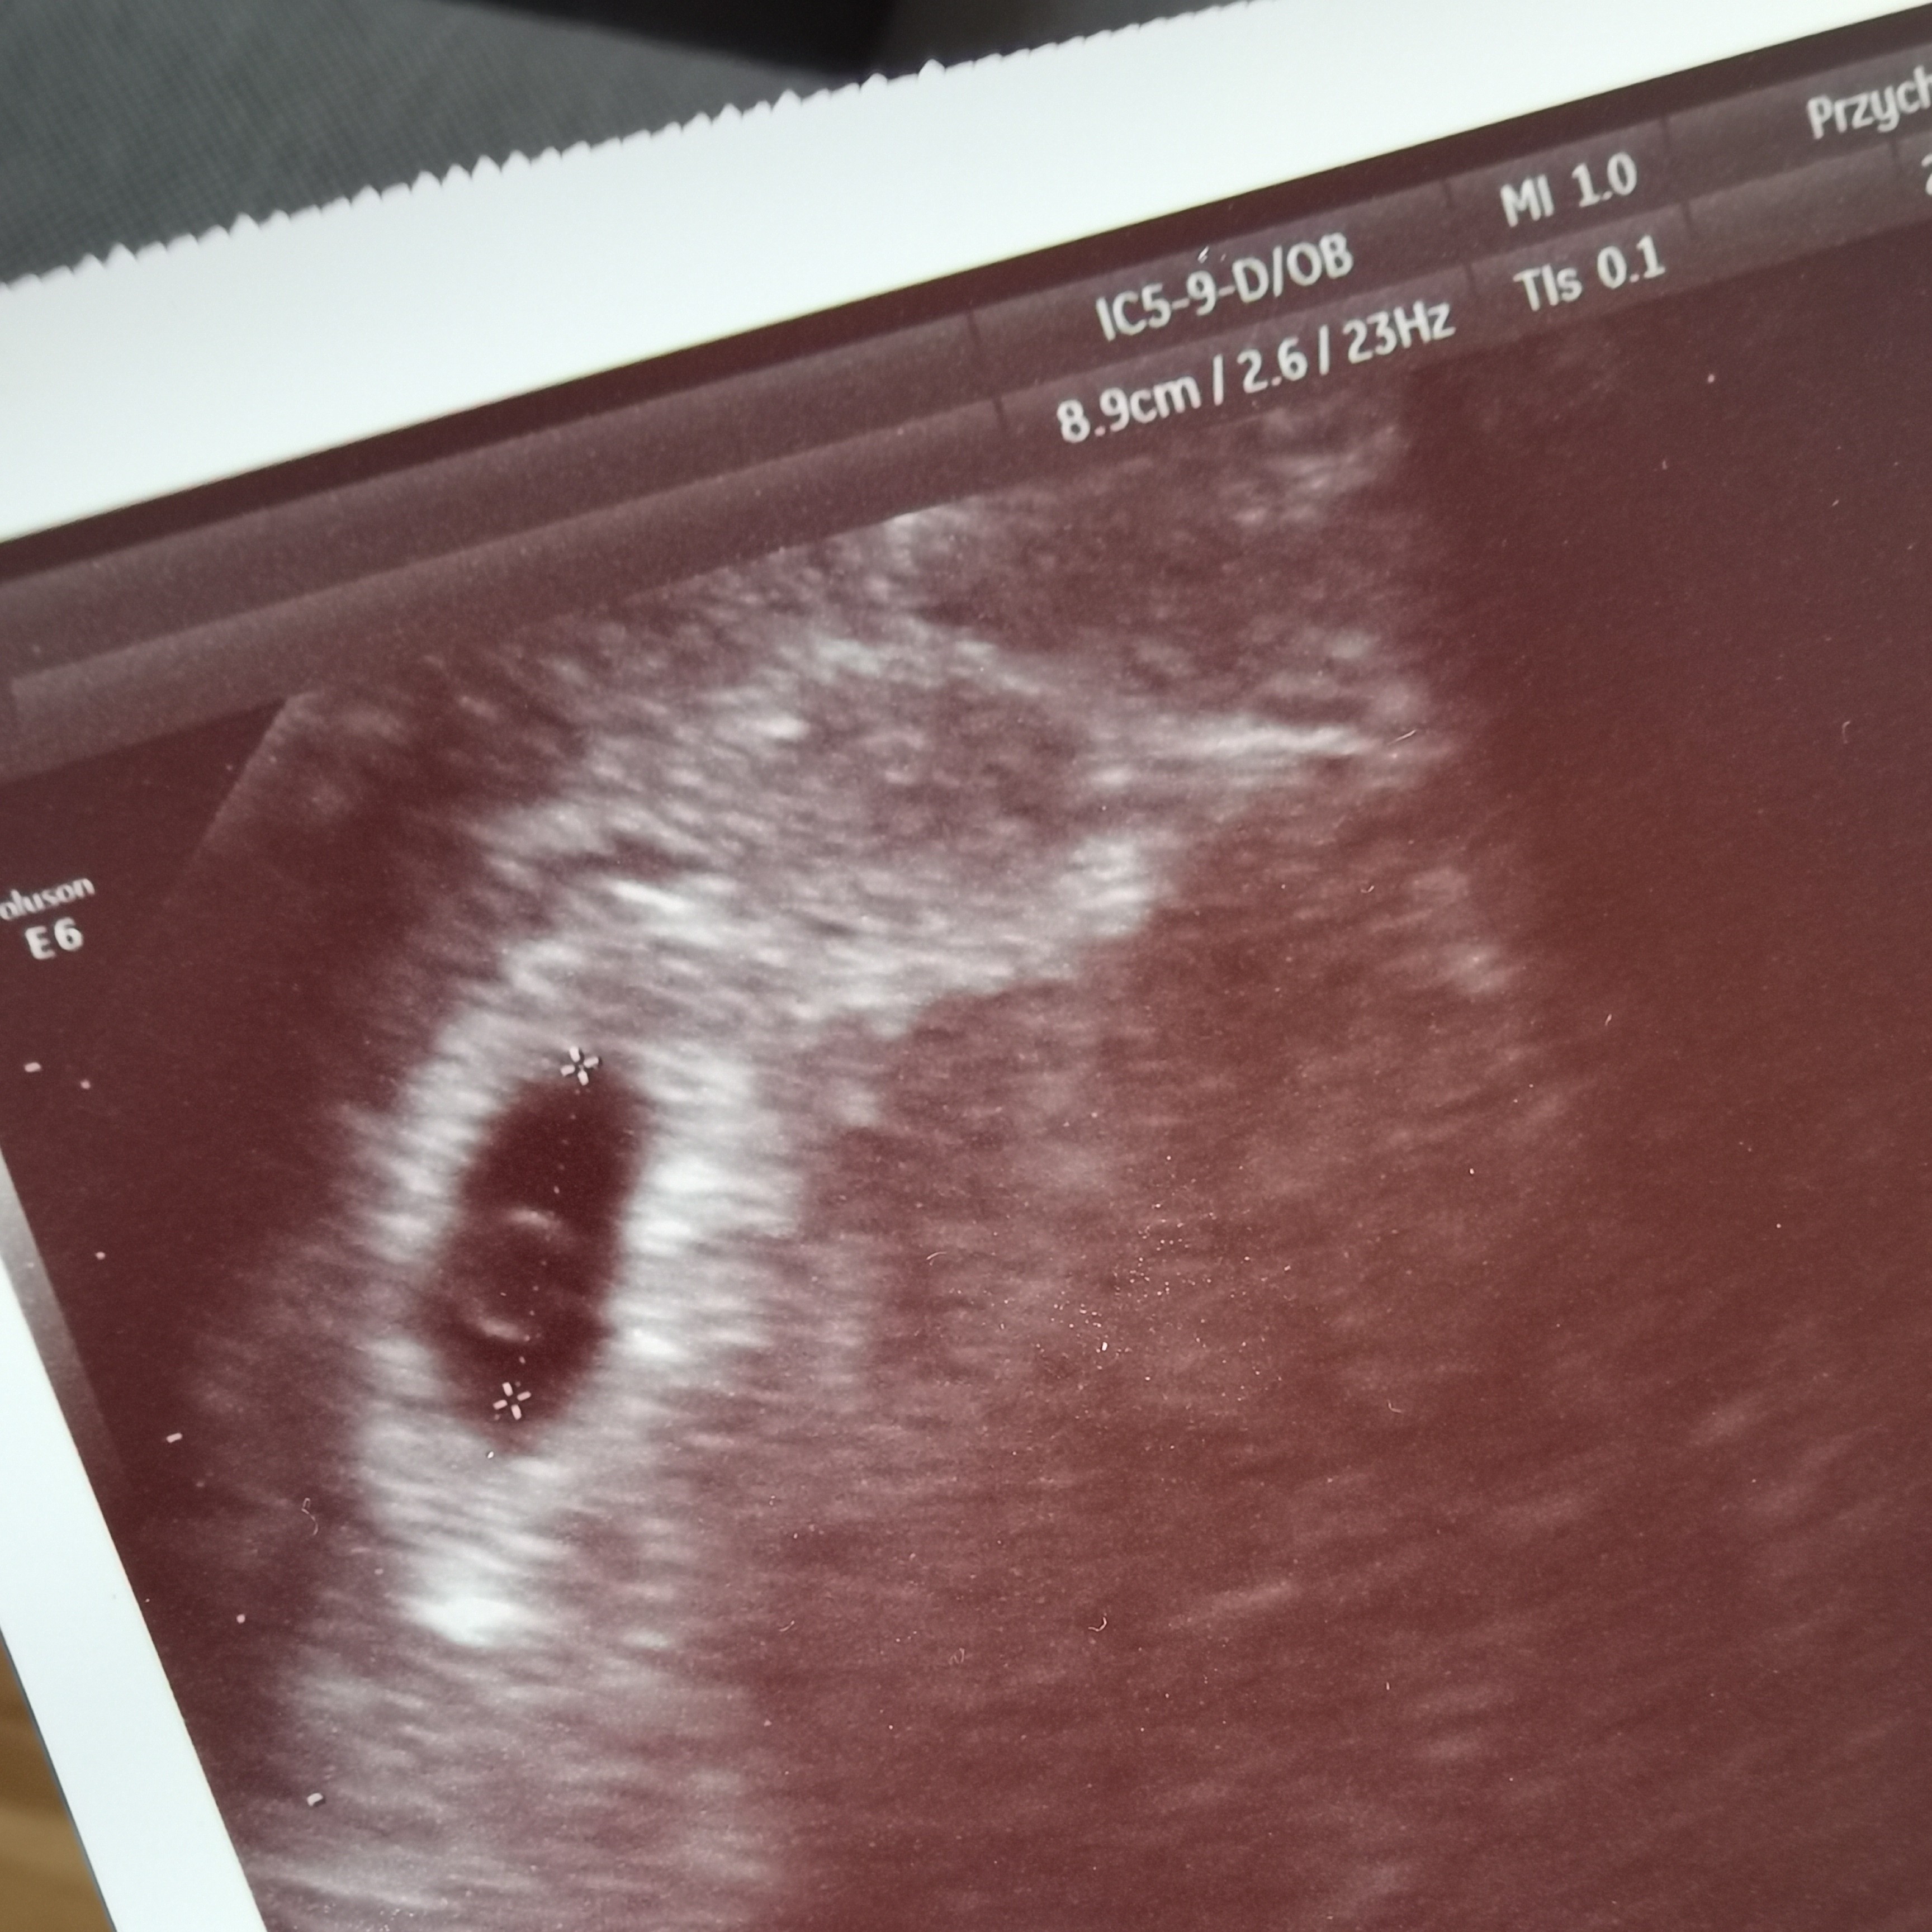

Pokazesz jak wygladal scan?Taak masz rację, teraz patrzę na usg i jest zaznaczony cały pęcherzyk, a nie tylko żółtkowy![]()

Proszę bardzoPokazesz jak wygladal scan?Mialam napisac to samo co blanny, zarodek pojawia sie do 6mm pecherzyka zoltkowego. Super, ze jest wszystko dobrze